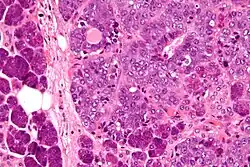

Micrograph of an epithelial-myoepithelial carcinoma (right of image). The epithelial component has a tubular morphology and is evident only focally (upper left of image). Benign serous glands (parotid salivary gland) are also seen (left of image). H&E stain.

This tumour is characterised by biphasic tubular structures composed of inner ductal and outer clear myoepithelial cells.